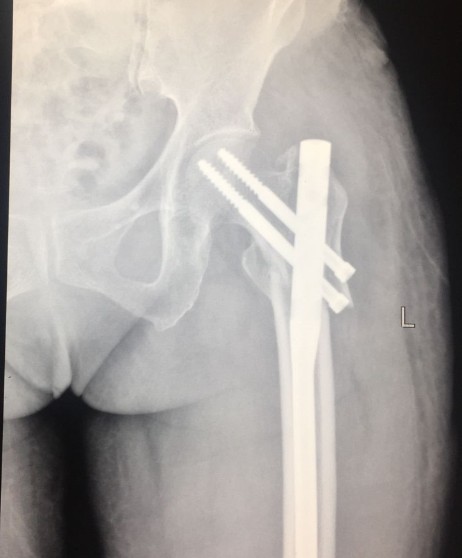

入院第二天,宜宾民心创伤骨科医院骨科主任为王奶奶成功实施了“左侧股骨近端粉碎性骨折切开复位髓内针内固定术”。

术后.png

半个月后,再次见到王奶奶时,她已经能扶拐下地行走,正在进行术后的康复锻炼,目前,王奶奶已经康复出院!